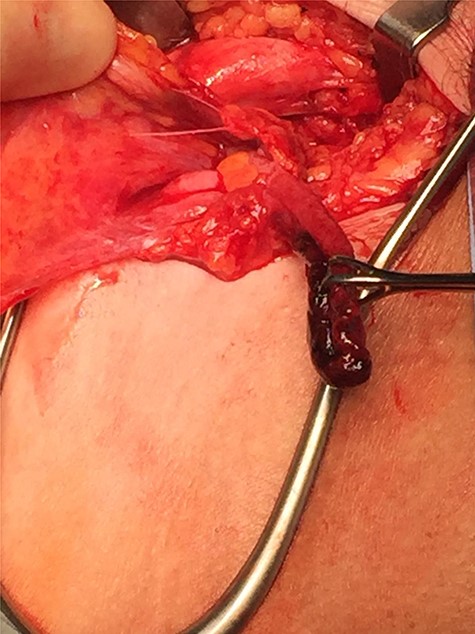

An incarcerated femoral hernia was diagnosed clinically and previous hematological investigations and imaging studies were reviewed. Full blood count, urea and electrolytes and liver function tests were within normal limits. Inflammatory markers including C-reactive protein had not been tested for preoperatively. The patient’s staging computed tomography (CT) thorax, abdomen and pelvis (performed a month before surgery) had shown fluid in the right inguinal region, appearing to lie within a small hernia (Fig. 1). A decision was made by the treating team to proceed with a joint procedure. The patient was consented for simultaneous mastectomy with axillary clearance and hernia repair.

Axial contrast-enhanced CT showing hernial sac containing fat and simple fluid but no appendix (red arrow).